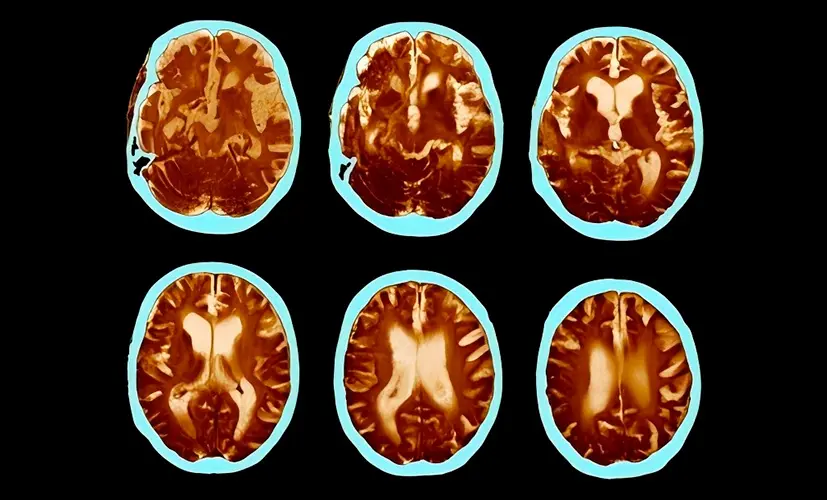

3. Brain fog leading to chronic fatigue

Inflammation spreads from the brain to affect overall neurological health. The result? A mind that slowly shuts down. Mental exhaustion becomes your new norm-struggling to think clearly, day after day, as your body weakens. I've seen individuals beg for relief that never arrives.

4. Stroke caused by impaired blood flow

Cognitive decline is often the first sign of poor vascular health-not just in the brain. If ignored, a clot could strike, causing a stroke. I've seen seemingly healthy 45-year-old individuals on the operating table, fighting for their lives, all because they assumed their "lapses" were just a part of aging.

What's the connection between brain vessels, heart disease, and cognitive function?

– Why do people with cognitive decline often also suffer from heart disease and clogged brain vessels?

– The blood vessels throughout the body are closely connected. If the vessels in the brain are clogged with plaque, they receive fewer nutrients. That's where cognitive decline and other serious issues begin.

The same goes for the heart. People with cognitive decline are 59% more likely to develop coronary artery disease or atherosclerosis, and 34% more likely to suffer a stroke. As we've discussed, cognitive decline can also lead to depression, which further increases the risk of cardiovascular disease. Add in the overuse of Aricept, which negatively impacts brain function-and suddenly, the person suffering from cognitive decline is almost guaranteed to face fatal neurological complications.